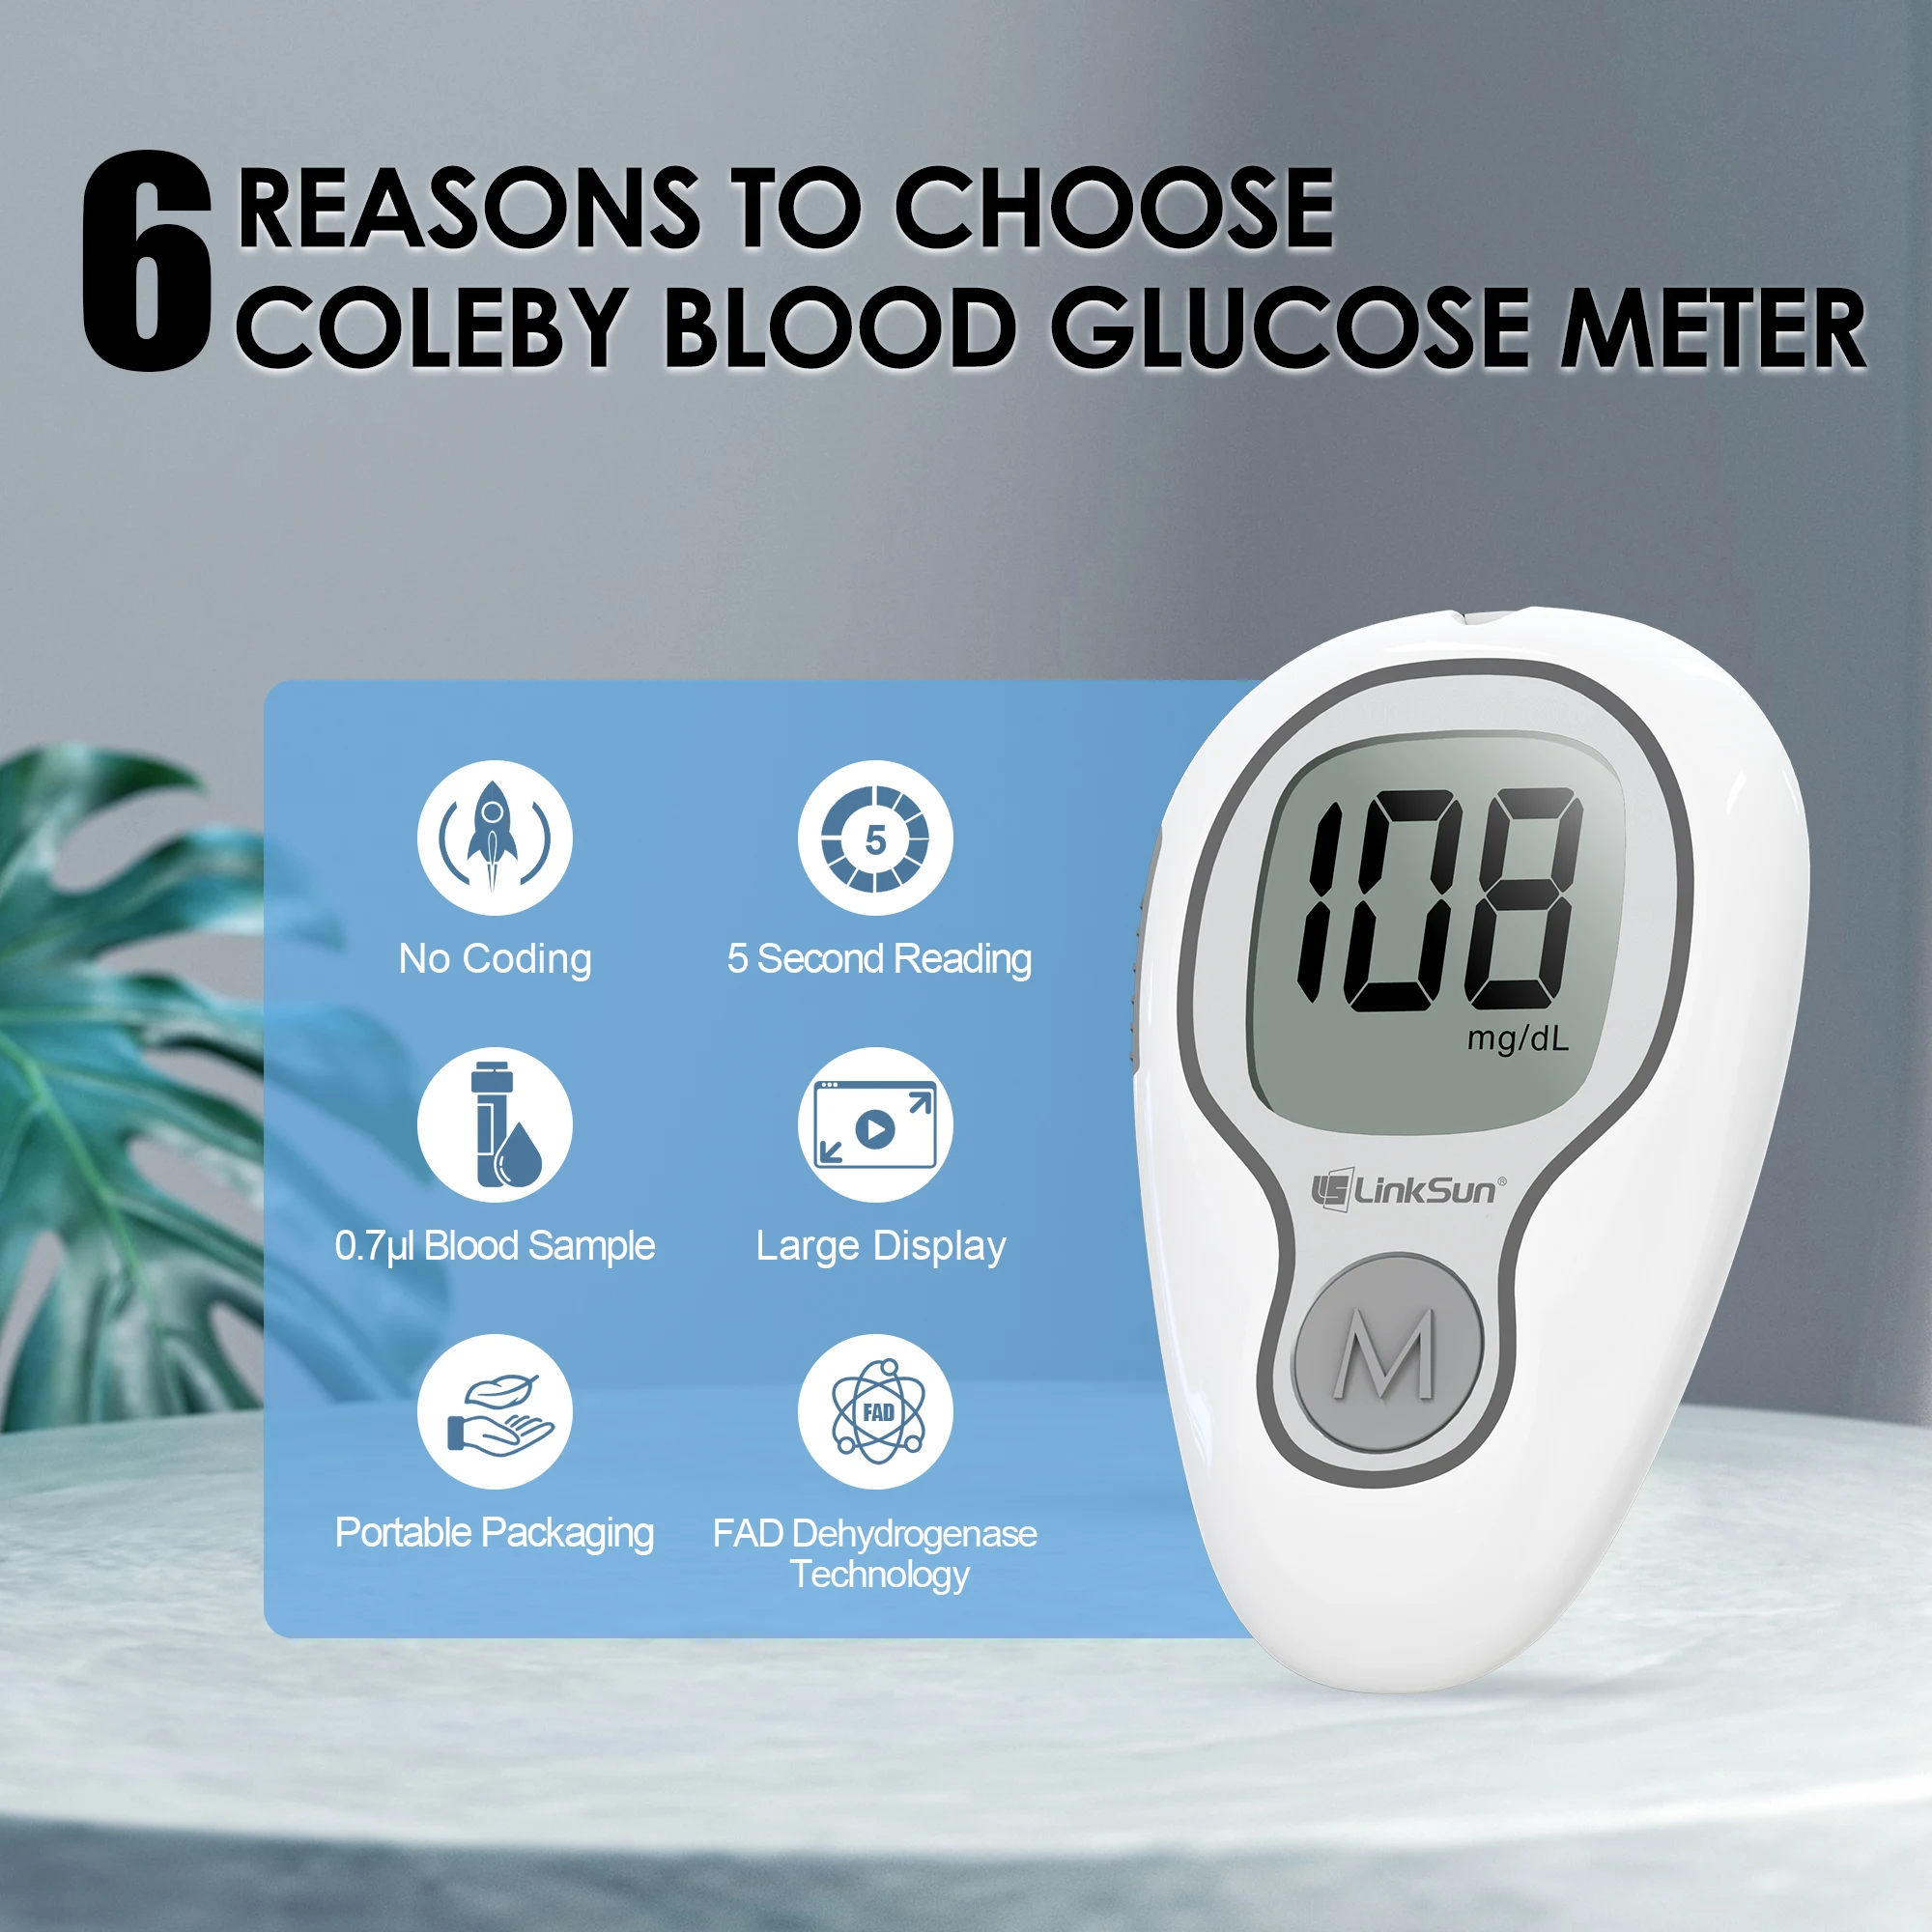

Bluetooth: No

Brand Name: Linksun

Certification: CE

Choice: yes

Function: Be used to measure the glucose content in th

Hign-concerned Chemical: None

Is Batteries Included: No

Item Name: glucometer complete kit

Item Type: blood glucose

Material: Medical PVC

Measurement Range: 20-600mg/dl

Memory groups: Large 500 memories

Minimum Sample Size: 0.7 μL

Model Number: G-425-3

Number of Pieces: One Unit

Operating Condition: 10°C~40°C, RH<=80%

Origin: China Mainland

Storage Condition: -20°C~55°C, RH<=93%

Suitable for: Diabetics, seniors, pregnant

Test Time: 5s

Test strips packing: Bottled packing

Without Bar Code: Automatic calibration

glucometer 2: Blood glucose meter

glucometer 3: Glucose test strips

glucometer 4: diabetes testing Kit

glucometer 5: digital glucometer

glucometer 6: blood sugar meter

glucometer 7: sugar test machine

glucometer 8: diabetes accessories

glucometer 9: blood sugar monitor

semi_Choice: yes

LinkSun Blood Glucose Meter G-425-3 Glucosemeter Kit No Code For Diabetes Tester 10/50/100pcs Strips Medical Blood Sugar Monitor

Note:

1, Batteries are not included in package because of aviation restrictions.

2, Please use up the test strips within 3 months once you open the vial.

Features:

Accurate and Reliable Testing: G-425-3 blood glucose meter adopts advanced detection and production technology to provide more accurate and reliable results. It has an accuracy of up to ±12%, complies with the ISO 15197:2013 standard, and has not had any market recalls in the past 20 years.

Simple and Easy to Use: The blood glucose meter adopts a no-coding design and can be tested after inserting the test strip; a quick guide is included in the package, which clearly lists the test steps and is easy to follow; if you have any operational problems, we are always available to provide help and tutorials on the blood glucose monitoring system video.

Quick Test Time: Ready out of the box, just 5 seconds countdown for daily testing. 5 levels of lancing strengths with 5 the deepest depth suits different types of finger skins.

Large Screen Display: Compared with most blood glucose meters, our display screen is larger and the results are displayed more clearly, suitable for the elderly to read.

Specifications:

Brand: LinkSun

Product size: 90*54*23mm

Data Reading:LCD Screen

LCD Size:29*30mm

Test time: 5s

Blood volume: 0.7μl

Power: 2*AAA batteries(Not included)

Memory: Large 500 Memories

Certificate: CE,Rohs

Measuring range: 20 mg/dL - 600 mg/dL (1.1 mmol/L - 33.3 mmol/L)

Operating condition: 10-40℃, RH≤80%

Storage condition: -20-55℃, RH≤93%

Set Size: 100*175*54mm(L*W*H)

Please pay attention to the package differences, and select whichever you like.

Package include:

[G-425-3-10suit] :1*Glucometer (No battery)+1*Lanceing device+10*test strips+10*Lancets

[G-425-3-50suit] :1*Glucometer (No battery)+1*Lanceing device+50*test strips+50*Lancets

[G-425-3-100suit] :1*Glucometer (No battery)+1*Lanceing device+100*test strips+100*Lancets

[only 100pcs strips]: 100*test strips + 100*Lancets

[only 200pcs strips]: 200*test strips + 200*Lancets